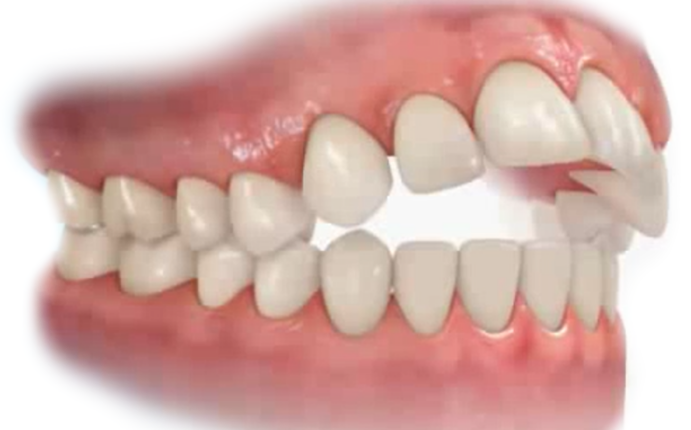

Occlusion And Malocclusion:

- Class I Malocclusion.

- Class II Malocclusion.

- Class III Malocclusion.